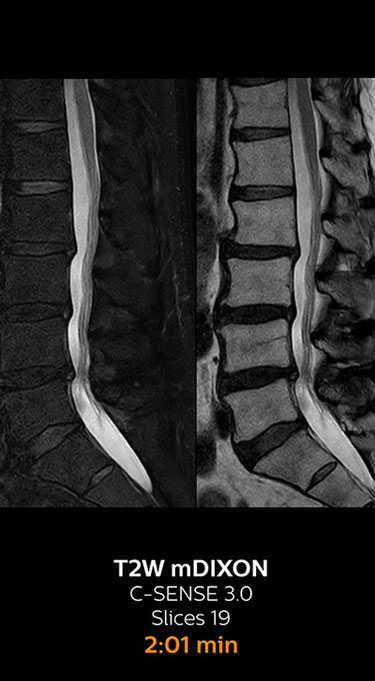

Fast MRI of lumbar spine

With Compressed SENSE, the scan time for the routine lumbar spine examination at KNC was reduced from 11:41 to 8:17 minutes,

which corresponds to 34% reduction.

MRI examination of lumbar spine with Compressed SENSE

MRI examination of the lumbar spine with Compressed SENSE

Ingenia 3.0T CX

Scan time 8:17 min. (was 11:41 min. without Compressed SENSE)